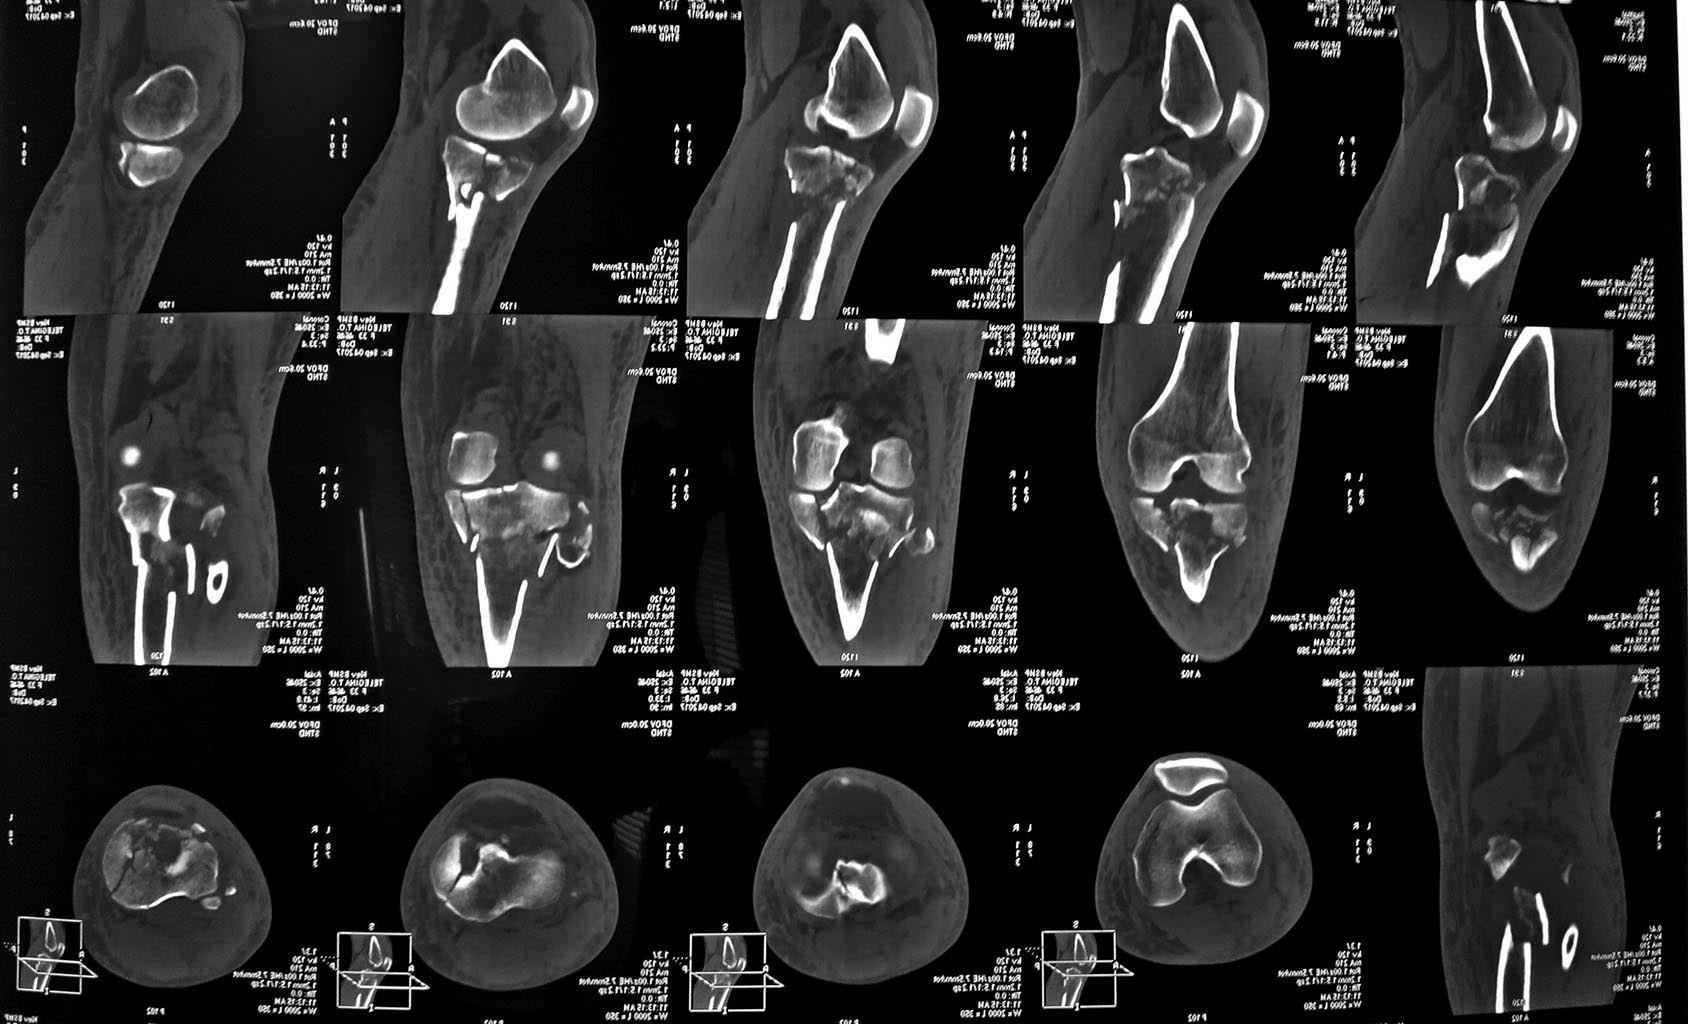

Добрый день, дорогие коллеги, прошу совета. Молодая пациентка с

переломом ПЭМ голени, фрагментацией fibular head и нейропатией peroneal

n.(подобное сочетание у нас не часто). Мягкие ткани компенсированы,

планируется реконструкция из 2-х доступов, однако

разделились мнения касательно целесообразности ревизии нерва,репозиции и

фиксации перелома fibular head. Считаю, что для ранней функции репозиция

и укрепление коллатерального комплекса необходимы. Спасибо.